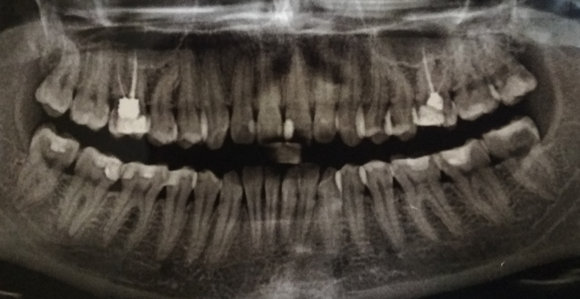

Здравствуйте! Есть ли у меня киста? Если да, то как срочно нужно делать операцию и как она называется?

Какой зуб вы имеете ввиду? Уточните. 18 и 48 зуб необходимо удалить. Далее расскажу после уточнения.